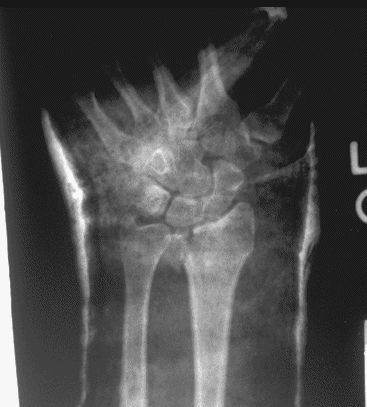

Case 1 Injury